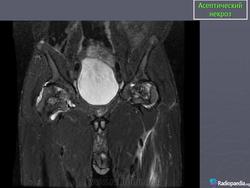

МРТ.  Аваскулярный некроз

http://www.radsource.us/clinic/0511